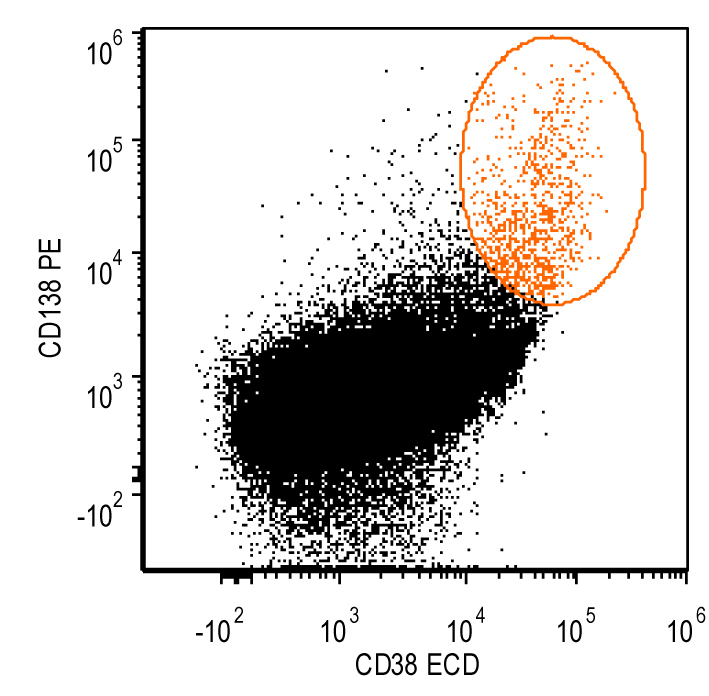

- Flow cytometry: monoclonal B cells with typical immunophenotype and monoclonal plasma cells

- Immunophenotype of LPL cells: IgM+, CD19+, CD20+, CD22+, CD25+, CD10-, CD23-, CD103-, variable CD138

- Immunophenotype

- Positive: IgM, CD19, CD20, CD22, CD79a, CD25 and CD38 frequent expression

- Negative: CD5, CD10, CD103, CD23; however, CD23 expression is not uncommon in some cases

Flow cytometry description

Flow cytometry images

Contributed by Ling Zhang, M.D. and Caroline An, M.D.